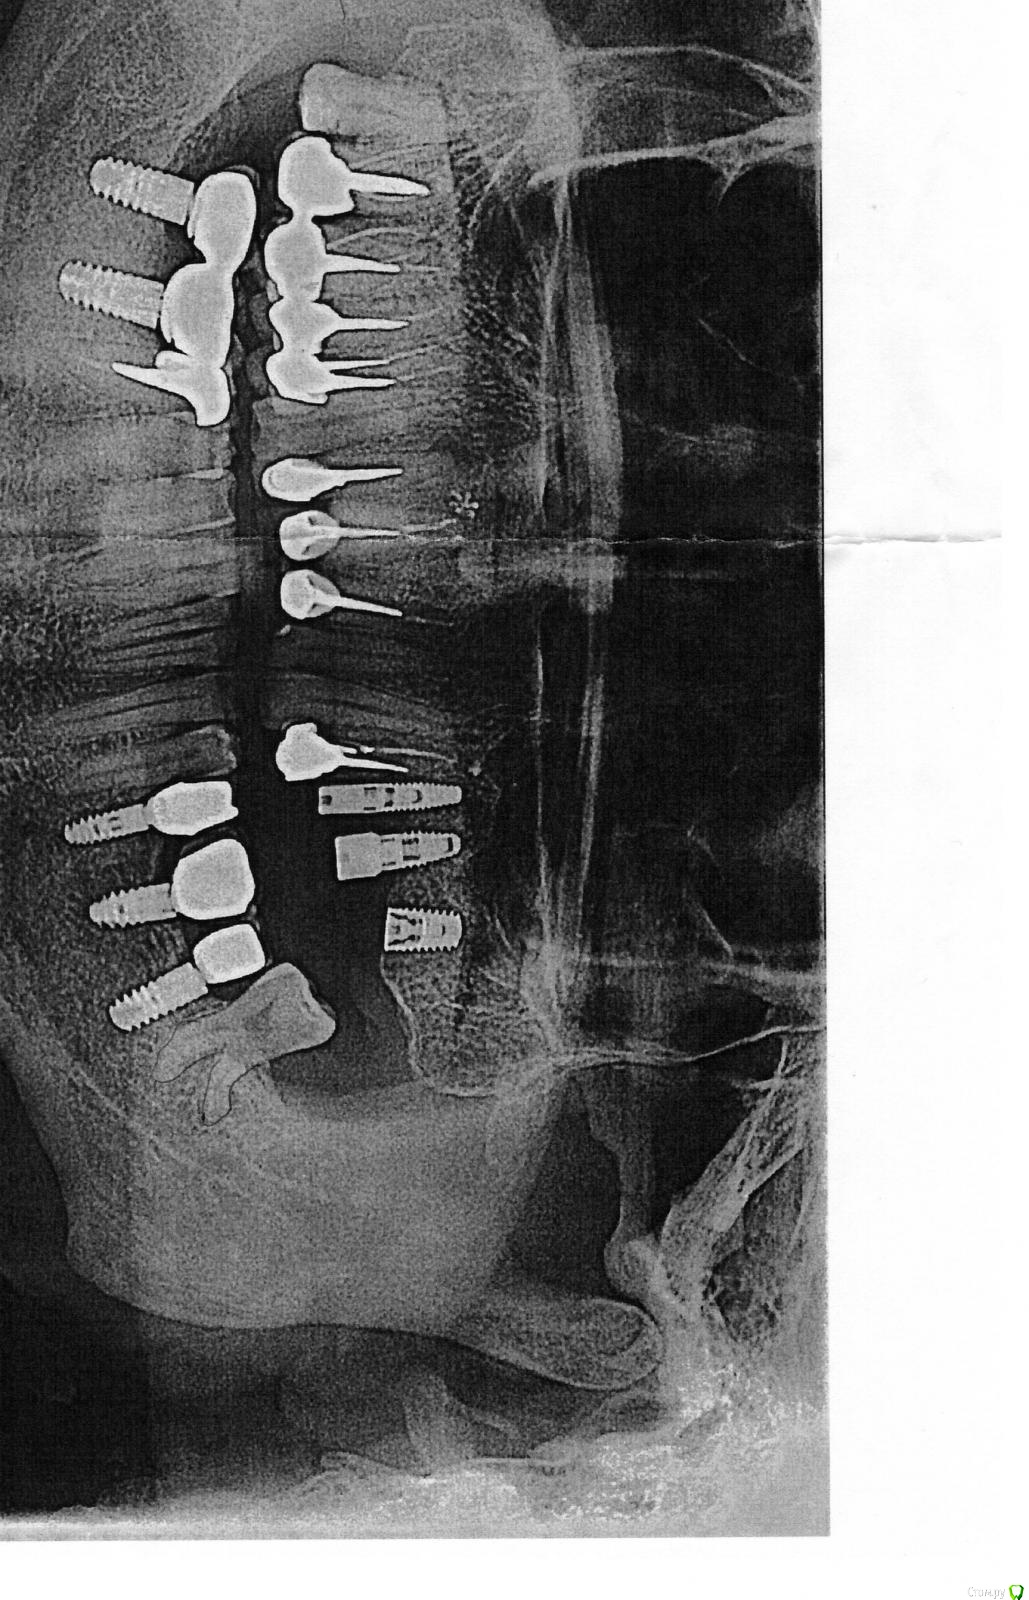

Bier Опубликовано 16 ноября, 2018 Поделиться Опубликовано 16 ноября, 2018 снимки покажите. 1 Ссылка на комментарий

Slacker1 Опубликовано 16 ноября, 2018 Автор Поделиться Опубликовано 16 ноября, 2018 снимки покажите. Ссылка на комментарий